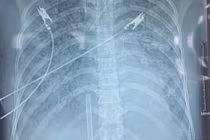

Người bệnh được hỗ trợ tim phổi nhân tạo (ECMO) liên tục tại khoa Hồi sức tích cực – Chống độc (ICU) - Ảnh BVCC

Chị Thơ lập tức được chuyển vào khoa Hồi sức tích cực và Chống độc (ICU) để khởi động quy trình hồi sức tim mạch tích cực. Lúc này, người bệnh tiếp tục rối loạn nhịp thất nặng kèm sốc tim tiến triển. Các biện pháp hồi sức thông thường không đủ để duy trì tuần hoàn.

Trước tình huống nguy kịch, ThS.BS Huỳnh Khiêm Huy, Trưởng khoa Hồi sức Ngoại Tim mạch cùng ê-kíp quyết định đặt hệ thống ECMO (oxy hóa máu ngoài cơ thể). Đây là một kỹ thuật hồi sức tim phổi tiên tiến thường được áp dụng trong các ca ngưng tim hoặc sốc tim kháng trị. Hệ thống ECMO hoạt động như “tim – phổi” tạm thời, giúp bơm máu và trao đổi oxy cho máu, tạo điều kiện cho tim được nghỉ ngơi, phục hồi.

Hệ thống ECMO được đặt và khởi động trong vòng 30 phút. Máu người bệnh được dẫn ra ngoài cơ thể, qua màng trao đổi oxy rồi bơm trở lại động mạch chủ, đảm nhận nhiệm vụ mà trái tim yếu ớt không còn đủ sức làm.

Trong 72 giờ tiếp theo, ECMO vận hành liên tục, từng nhịp bơm của máy đồng hành cùng nỗ lực hồi sinh trái tim thật. Khi các xét nghiệm cho thấy men tim giảm, EF cải thiện lên 40%, bác sĩ bắt đầu giảm dần hỗ trợ và rút ECMO an toàn.